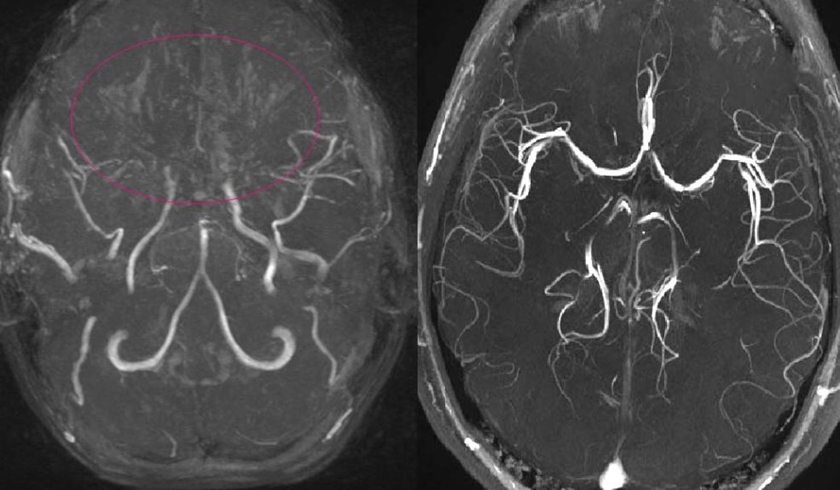

모야모야병은 뇌질환입니다. 뇌혈관이 좁아지거나 막히게 되어서 허혈이 진행하게 되면 뇌기저부에 이상혈관이 만들어 지게 되는데 이상혈관의 모양이 연기가 피어오르는 모양처럼 보인다고 합니다.